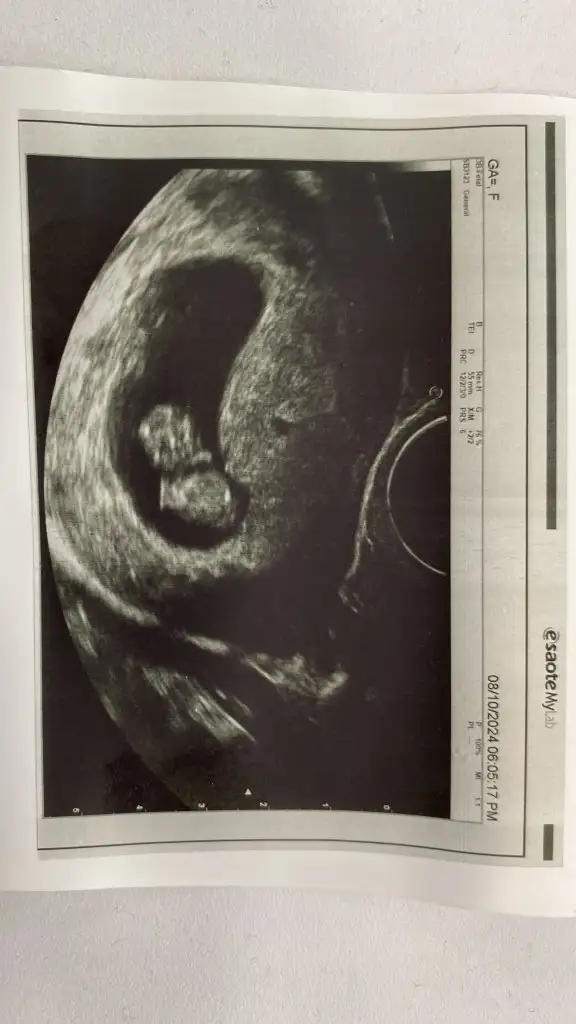

Kimse yok mu12 haftalik karindan ultrason rica etsem cinsiyet tahmini yapabilir misiniz

Başka foto yok mi12 haftalik karindan ultrason rica etsem cinsiyet tahmini yapabilir misiniz

Benimkine de baksanız ilk ve çok merak ediyorumBaşka foto yok mi

Bacak arası fotosu bu doktor kız diyor ama ben hala erkek hissediyorummmCanım hiç belli olmuyor bacak kısımları anlayamayuz böyle

Evet doktor kız dedi ama ben ısrarla erkek hissediyorummm 14. Haftada söylediBence kız bir an öyle hissettim nedenini bilmeden ama tabi ne olursa olsun sağlıklı olsun

Evet doktor kız dedi ama ben ısrarla erkek hissediyorummm 14. Haftada söyledi

Bacak arasını boş gördüğü için demiştir kızda yanılma payı var detaylı ultrasona girene kadar bende erkek hissediyorum ama daha belli değil 15 hafta 2 günlük benim bebişim deEvet doktor kız dedi ama ben ısrarla erkek hissediyorummm 14. Haftada söyledi